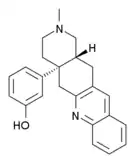

The pharmacodynamic response to an opioid depends upon the receptor to which it binds, its affinity for that receptor, and whether the opioid is an agonist or an antagonist. For example, the supraspinal analgesic properties of the opioid agonist morphine are mediated by activation of the μ1 receptor; respiratory depression and physical dependence by the μ2 receptor; and sedation and spinal analgesia by the κ receptor. Each group of opioid receptors elicits a distinct set of neurological responses, with the receptor subtypes (such as μ1 and μ2 for example) providing even more [measurably] specific responses. Unique to each opioid is its distinct binding affinity to the various classes of opioid receptors (e.g. the μ, κ, and δ opioid receptors are activated at different magnitudes according to the specific receptor binding affinities of the opioid). For example, the opiate alkaloid morphine exhibits high-affinity binding to the μ-opioid receptor, while ketazocine exhibits high affinity to ĸ receptors. It is this combinatorial mechanism that allows for such a wide class of opioids and molecular designs to exist, each with its own unique effect profile. Their individual molecular structure is also responsible for their different duration of action, whereby metabolic breakdown (such as N-dealkylation) is responsible for opioid metabolism.

Morphinan derivatives